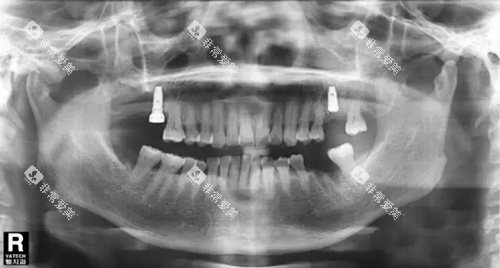

口腔修复科主要负责修复各种缺失牙。常见的修复方法有活动假牙、固定假牙和种植牙等。活动假牙价格较为便宜,适合大多数缺失牙患者,但佩戴起来可能会有一些不适感。固定假牙美观舒适,咀嚼功能较好,但需要磨除一定的邻牙组织。种植牙则是一种较为靠前的修复方法,它可以模拟天然牙的形态和功能,不需要磨除邻牙,但价格相对较高。